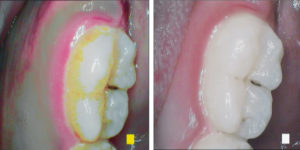

SoproCARE in Perio mode highlights different structures SoproCARE in Perio mode highlights different structures

SoproCARE in Perio mode (left) and Daylight mode (right) SoproCARE in Perio mode (left) and Daylight mode (right)

The simple beauty of ACTEON’s “I Promise” campaign is that by using the SoproCARE camera, your hygiene team will more easily be able to detect inflammation caused by periodontal disease. The patient will be able to view powerful images that illustrate the severity of the plaque buildup and inflammation present in their own mouth. This entire movement will empower dentists and hygienists to partner together to diagnose disease and then treat it.